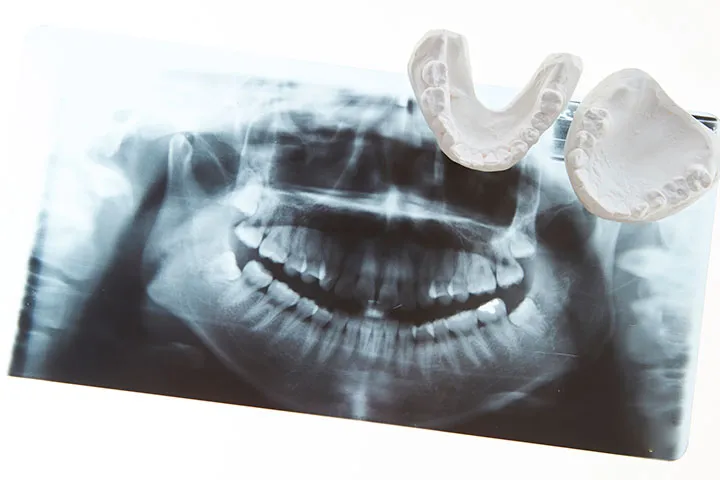

下顎前突とは?

下顎前突とは、下顎の骨が前方に出ている、または上顎の成長が不足していることで、下の歯が上の歯より前方に位置してしまう状態です。多くの場合、前歯が反対咬合 (クロスバイト) になります。